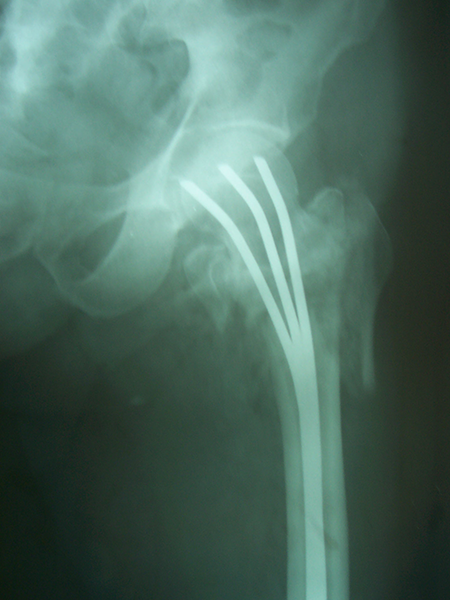

Case:9 Comminuted Intertrochanteric Fracture

Patient aged 75 years with Comminuted Intertrochanteric fracture treated with closed reduction & Ender’s nailing.

Pre-op Ap

Pre-op Lateral

Post-op Ap

Post-op Lateral

Post-op Distal End